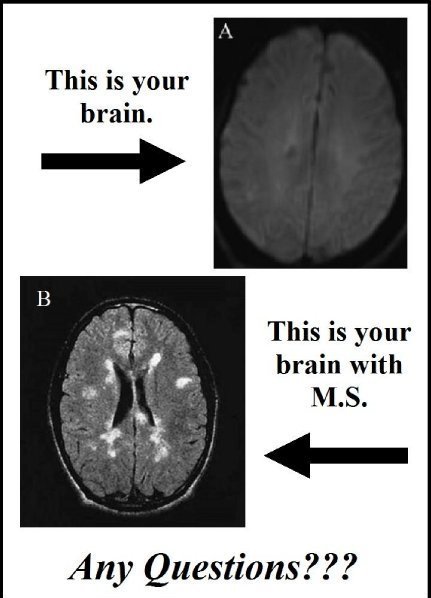

On Wednesday… now a full month of little to no taste, minimal feeling on the left side of my body, double vision and tremors in my right hand, I finally saw a neurologist. He showed me the video of my brain and two lesions on the right side which were causing my left side problems and lack of taste issues. He said the right side problems were a “leak-through” problem of the right side lesions and it could just have easily affected my mobility or speech. He sent me out with a stack of paperwork about 1/4 of an inch–saying that he wanted to rule out MS and lymphoma. Lymphoma! That wasn’t even on my radar — it was the first time I cried – and I tear up now feeling those emotions again. He wanted an urgent MRI of my spine to see if there were more lesions present and an urgent request for lumbar puncture.  The past two weeks have been a whirlwind. I have been paying people to poke me with needles – whether it be blood, contrast for the MRI of my spinal cord, or the lumbar puncture.

Brain lesions pic courtesy of Lucyand3cats.blogspot.com